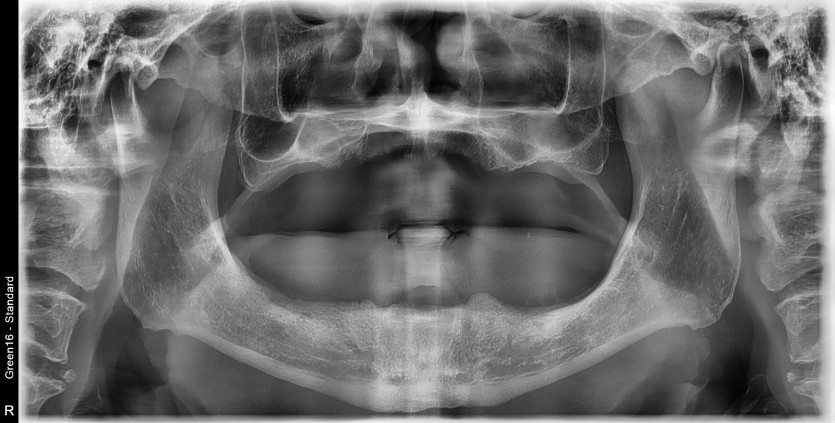

만 68세 전체 임플란트 증례

전체 임플란트 증례입니다.